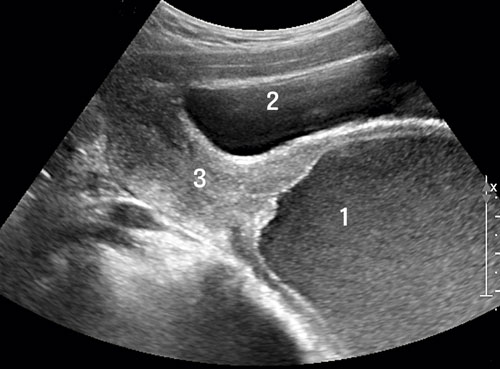

Fallbeskrivning Risk för långdragna symtom om adekvat undersökning inte genomförs